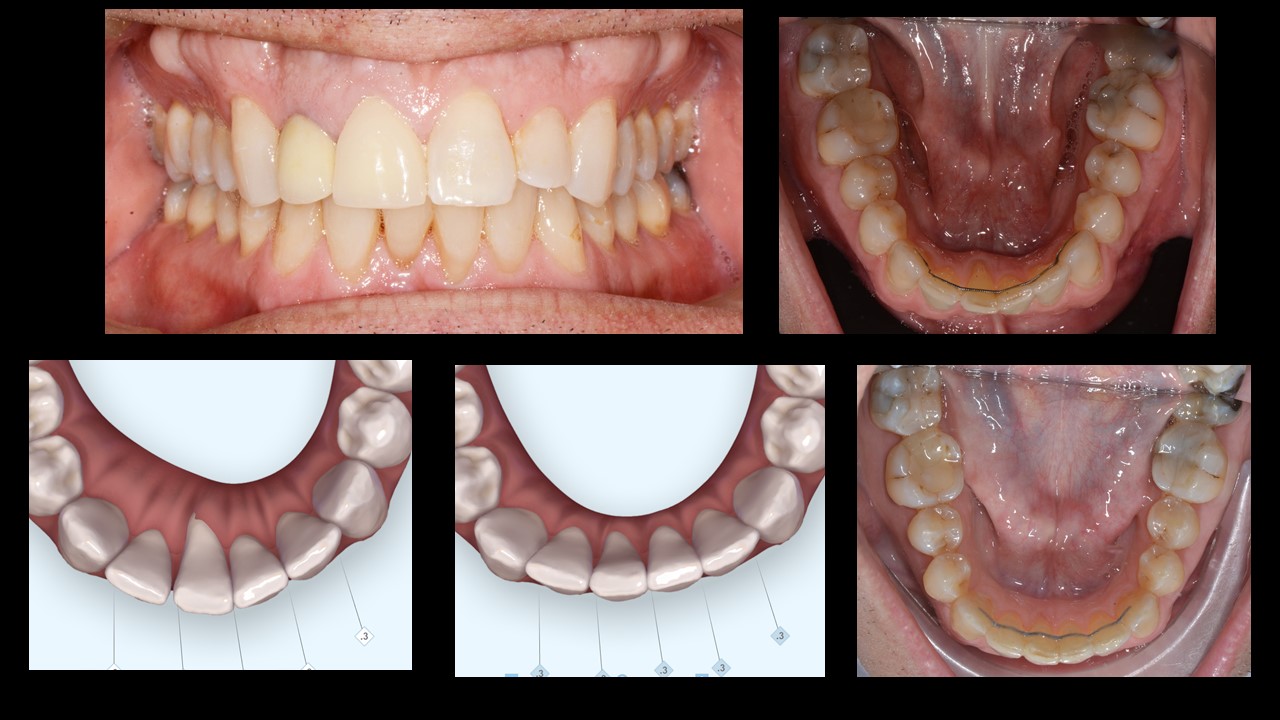

The fixed retainer holds the anterior segment at the crown level but has no effect on the root position. On the contrary, in some cases it creates a negative force on the root as seen in this case. Slow root torque on the tooth and clear aligners helped to correct the position of tooth #41. It is essential to continue to use the clear aligner as an active retainer for many years.